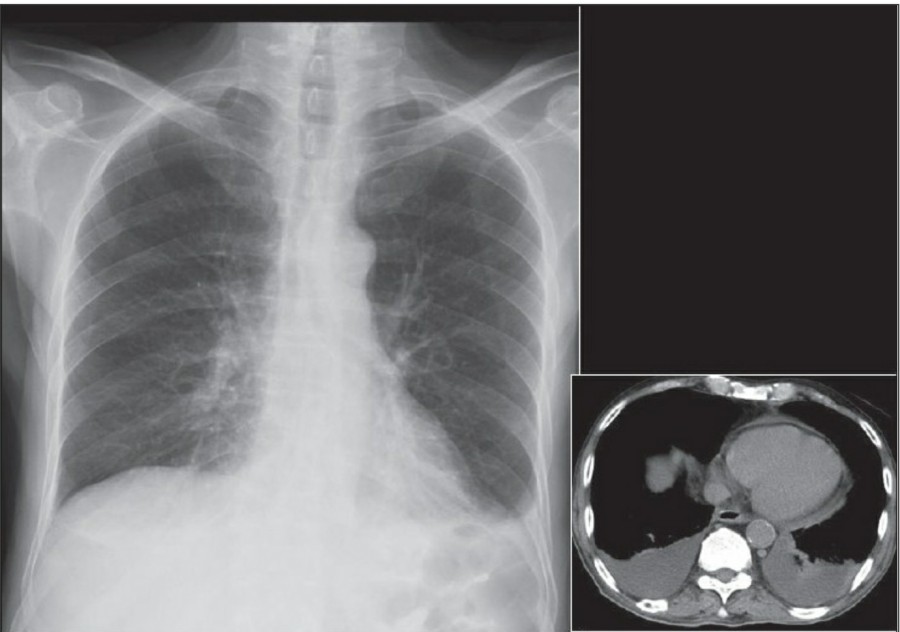

Pericardial effusions

Chest X ray에서 잘 보이지 않으며, 적은 양은 cardiomegaly와 감별이 힘들다. Chest X ray에서 Pericardial effusion은 cardiac silhouette의 변화와 함께 cardiomegaly로 보일 수 있는데, 이는 featureless, globular or "water bottle" shape로 나타나게 된다. 가장 좋은 진단 방법은 echocardiography다.